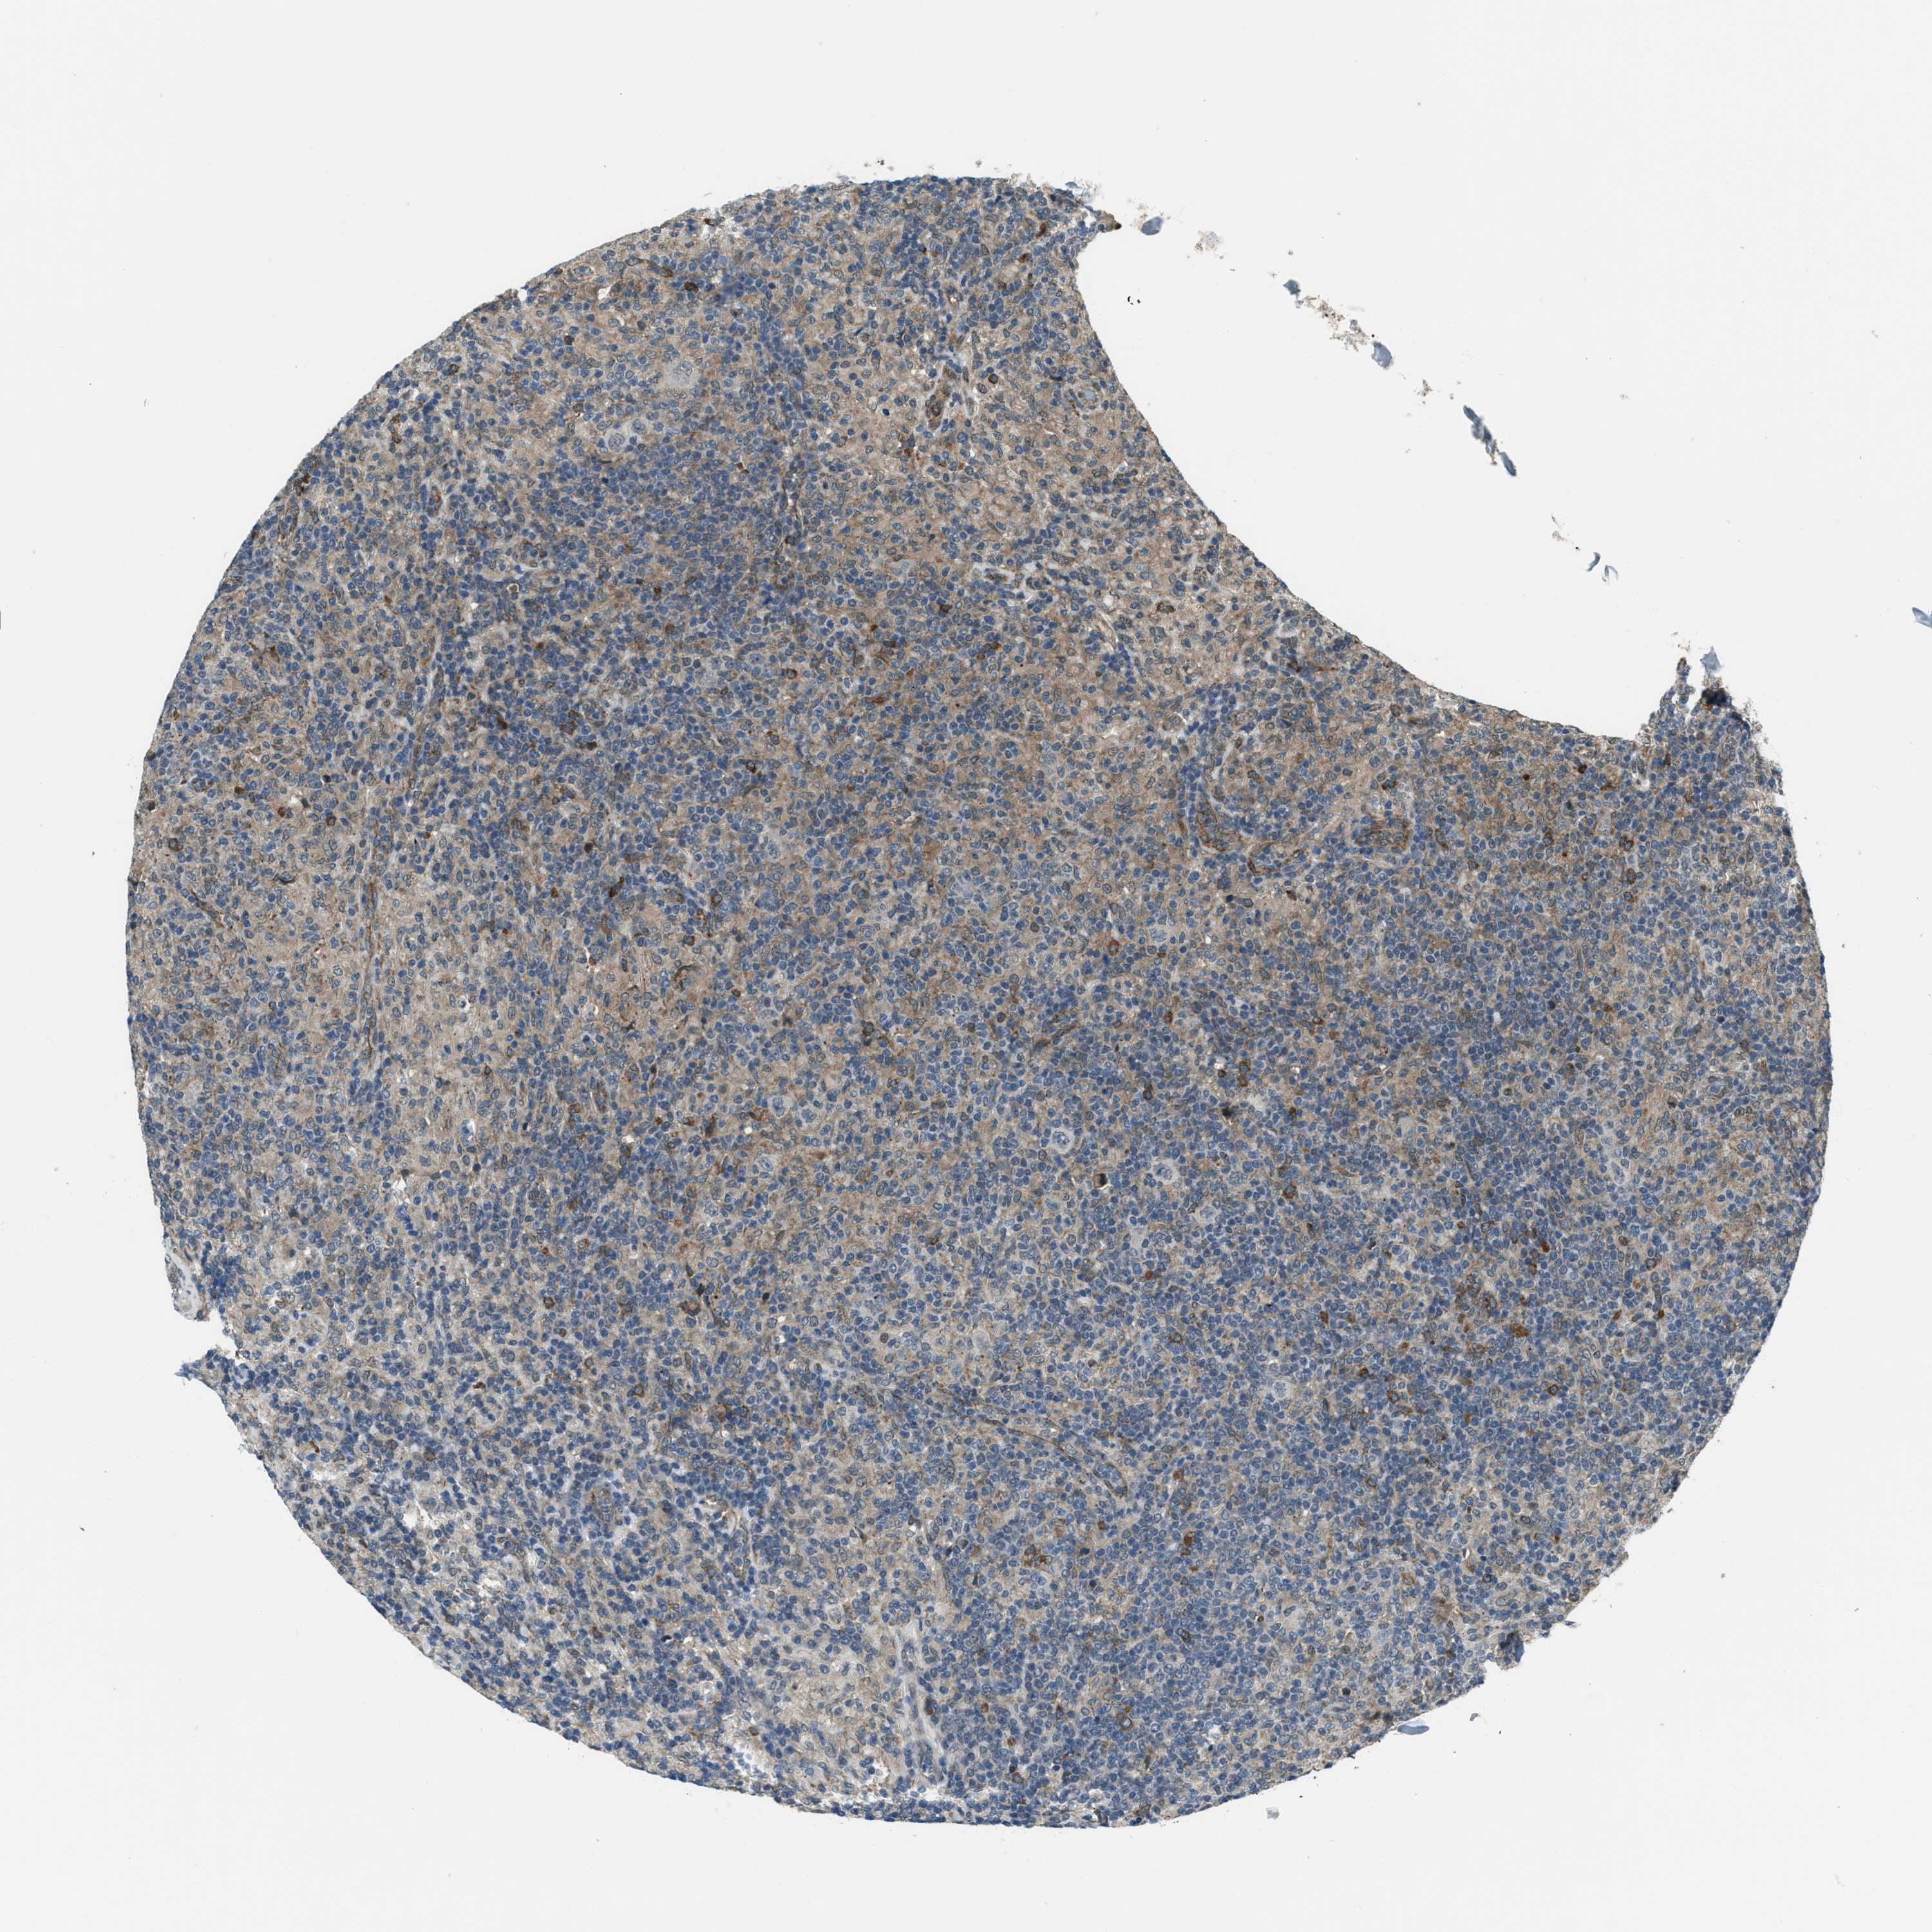

CANCER LYMPHOMA Show tissue menu

LYMPHOMA - Protein expressioni

A mouse-over function shows sample information and annotation data. Click on an image to view it in a full screen mode. Samples can be filtered based on level of antibody staining by selecting one or several of the following categories: high, medium, low and not detected. The assay and annotation is described here.

Each image is clickable and will lead to virtual microscopy that enables deeper exploration of all samples and also displays staining intensity scores, fraction scores and subcellular localization as well as patient and tissue information for each sample.

Antibody HPA020095

Antibody HPA020138

Antibody CAB010878

Antibody CAB080402

Staining

High

Medium

Low

Not detected

Intensity

Strong

Moderate

Weak

Negative

Quantity

>75%

75%-25%

<25%

None

Location

Nuclear

Cytoplasmic/membranous

Cytoplasmic/membranous,nuclear

Hodgkin's disease, NOS

Malignant lymphoma, non-Hodgkin's type, High grade

Malignant lymphoma, non-Hodgkin's type, Low grade